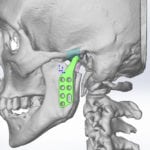

Псевдоартроз лечат исключительно оперативным путем. Хирурги иссекают фиброзную и хрящевую ткань, расположенную между костными фрагментами. Затем они заново сопоставляют отломки и фиксируют их системами чрескостной, накостной или интрамедуллярной фиксации. После этого пациент проходит полноценную реабилитацию.

Для стабилизации костных фрагментов могут использовать такие приспособления:

- аппарат Илизарова;

- штифты;

- винты;

- накостные пластины;

- интрамедуллярные стержни.

«Золотым стандартом» лечения псевдоартроза считается пересадка донорских или аутологичных кровоснабжаемых костных трансплантатов. Как правило, их получают из гребня подвздошной кости. Фрагменты костной ткани хорошо приживаются и не образуют фиброзных рубцов в месте пересадки.